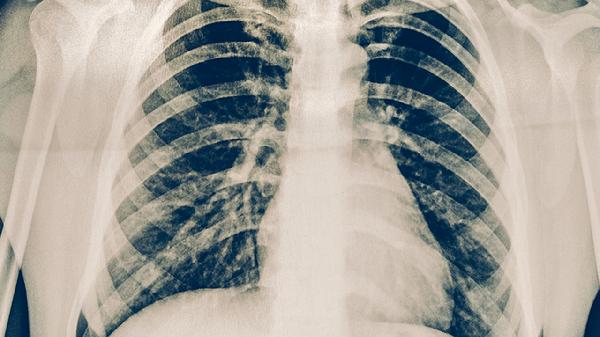

这是一位38岁的年轻女性,在体检中发现左上肺有磨玻璃结节,仅6mm,已经一年了。她复查了几次,发现这个结节一直没有变化,但是很多医生告诉她这个结节有点危险,结节里好像有空洞,这是肿瘤的特征,她很紧张,严重影响了生活。

因为她丈夫在做生意,她每天都很不安,家里的孩子也不想管教,所以她多次要求手术。但是,这个结节位置很深,如果要切除肺叶的话,会损害她的肺功能。所以我们经过三维重建,设计后,给她做了亚段切除手术。就是切掉她肺部的一部分,这样就很小,一小块就取下了这个结节。

这个结节手术结束后,证明是非典型的腺瘤增生。不典型的腺瘤增生是良性的疾病,是癌前病变,持续观察的话,有些患者会发展成原位癌和腺癌。但是它一点都不危险,长得非常慢,本来继续观察是没有问题的,但是她非常焦虑,导致各种身体的症状,胸痛,背痛,是因为她过度紧张。